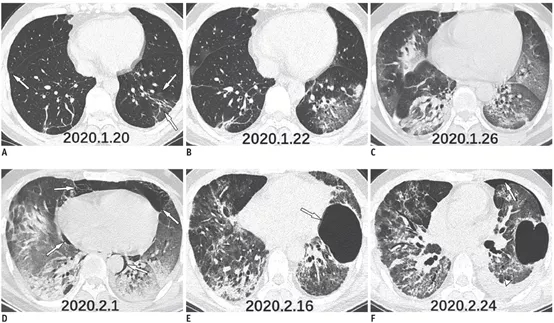

患者入院胸部CT提示左下肺叶毛玻璃影(图1A),在接下来的10天中,肺部病变的范围增加,并逐渐实变(图1B-D)。患者临床症状恶化,诊断为急性呼吸窘迫综合征,CT随访提示纵隔气肿(图1D,2A,B)。在支持治疗15天后,患者胸部CT提示肺部病变改善,纵隔气肿消失,左肺出现巨疱(图1E,F,2C,D)。八天后,CT提示左侧少量气胸和胸腔积液(图1F,2E,F)。

图1